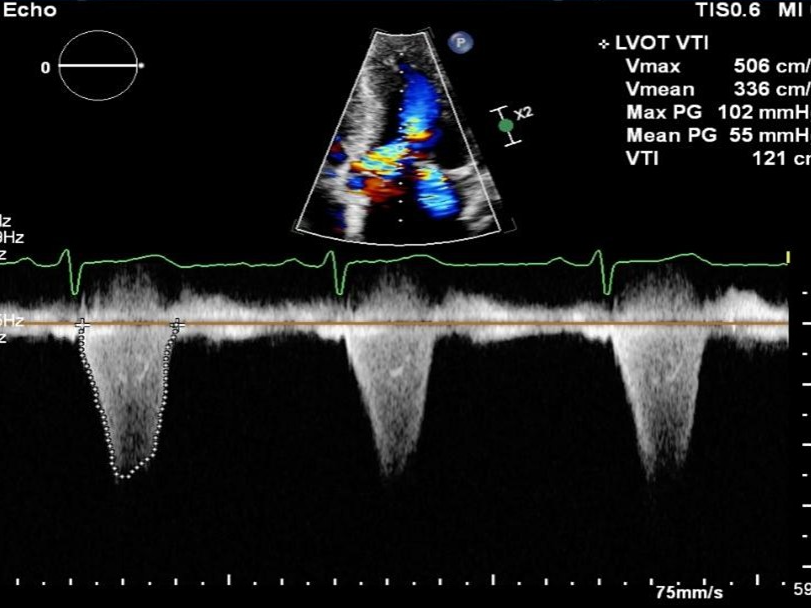

患者为一名40岁的女性。超声提示患者室间隔最大厚度为31.3mm,静息压差为102mmHg,负荷状态下为146mmHg。二尖瓣呈SAM征伴有少量反流。

术后左室流出道压差